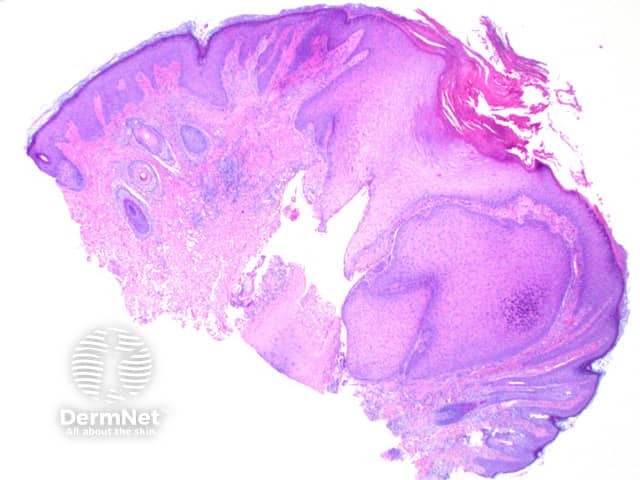

Scanning power view of chondrodermatitis nodularis helicis shows a wedge-shaped dermal alteration extending through to the superficial cartilage (Figure 1). The epidermis may show a focal zone of orthokeratosis and scale crust overlying moderate epidermal hyperplasia (Figure 2). Frequently there will be superficial epidermal ulceration. There is a zone of eosinophilic fibrinoid material overlying the affected area of cartilage, with the blurring of the superficial cartilage and altered staining (Figure 3). There may be adjacent perichondrial thickening.

Figure 1